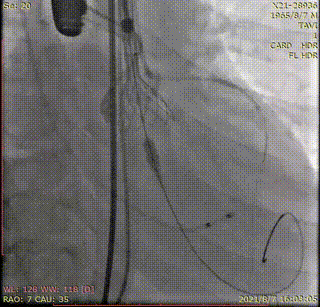

植入前冠脉造影

主动脉根部造影

直头导丝跨瓣

20mm球囊预扩

冠脉保护支架植入

AV23瓣膜释放到工作位

瓣膜完全释放

冠脉支架释放

植入后造影